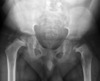

treatment options for deficiency below depends on what? Treatment options include?

In PFFD, treatment options depend on: (1) predicted length of the femur at maturity and (2) pelvic-femoral stability. This usually leaves the following treatment options: 1. If the hip joint is unstable (deficient femoral head and acetabulum, Aitken C/D), femoral-pelvic fusion is indicated. If the hip joint is stable (Aitken A/B) or is made stable, and the: a. foot of the involved limb lies proximal to the knee joint, Syme amputation (at 10-14mths) and knee fusion (at 3-4yrs) will allows the limb to bear an above-knee prosthesis. b. foot lies at knee level, Van Ness rotationplasty. c. limb shortening is minimal, limb lengthening +/- contralateral epiphyseodesis is indicated. ## Footnote principles of rotationplasty. They state that the requirements include: adequate plantar flexion strength, functional ROM, sensate foot and (attainable or braceable) proximal pelvic stability. They recommend against rotationplasty for PFFD in patients <12 yrs (to reduce late derotation).